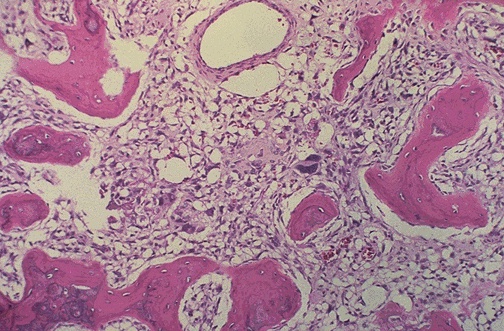

Image 8.3

The medium power microscopic appearance of the mass is shown here.